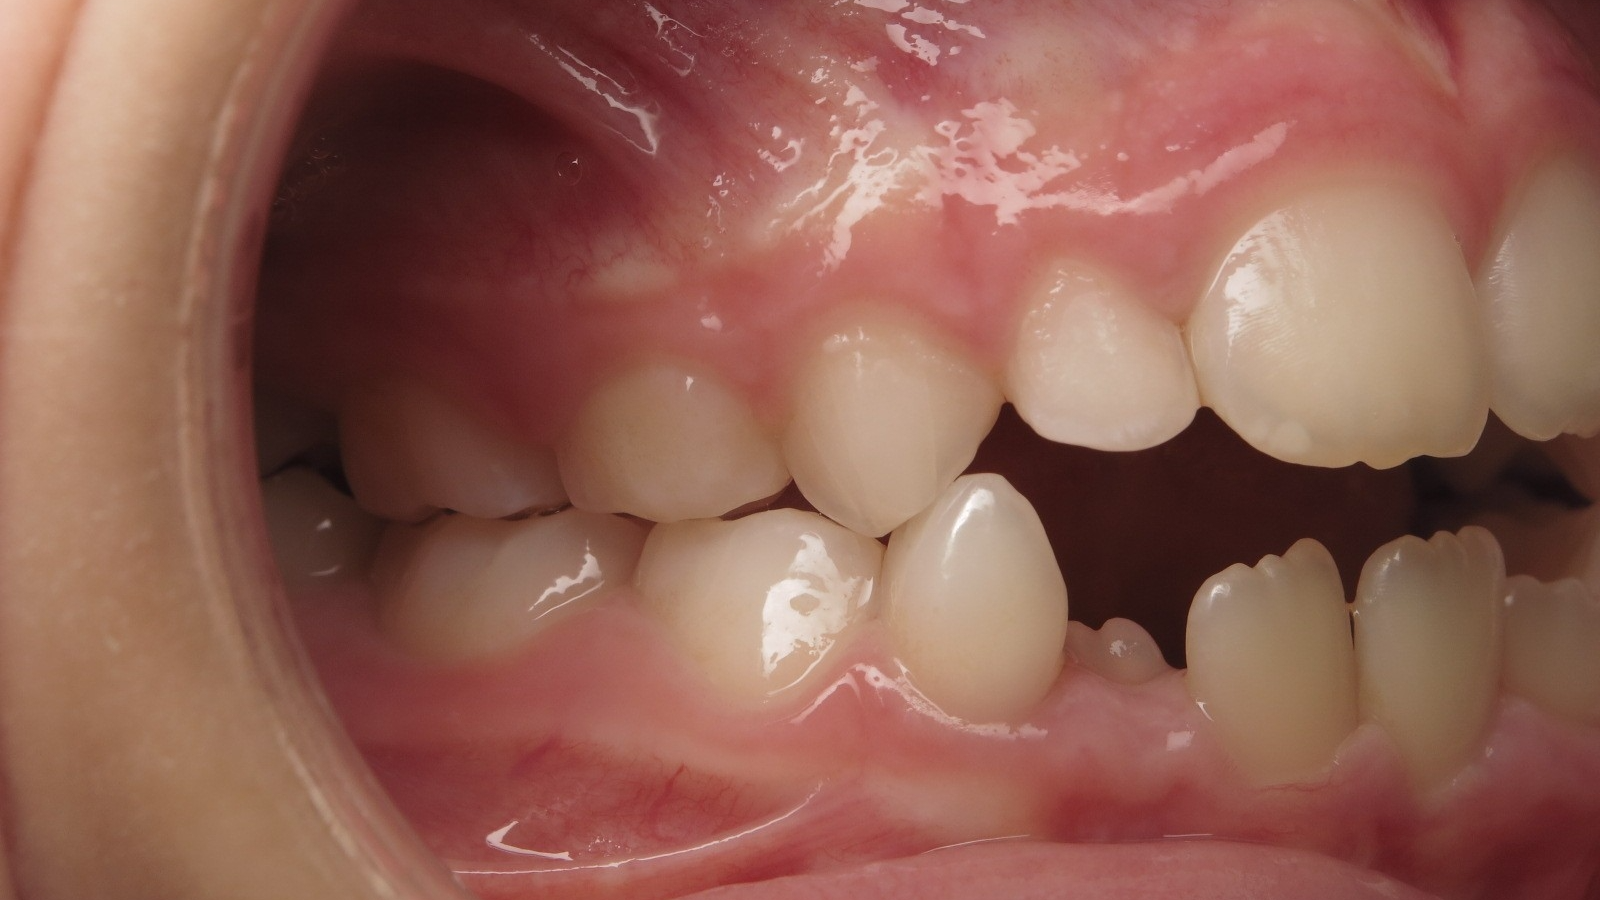

appareillage mobile pendant 5 mois

surveillance évolution de la dentition pendant 27 mois

appareillage mobile pendant 14 mois

sectionnel multibagues pendant 8 mois

bilan début et en cours de traitement